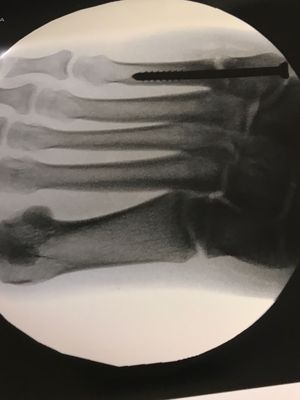

An image of a foot that has undergone 5th metatarsal surgery in an effort to stimulate and accelerate healing of a Jones fracture, bone was taken out of the heal of the patient on the same foot, this was used to stimulate the growth of bone in the fracture gap